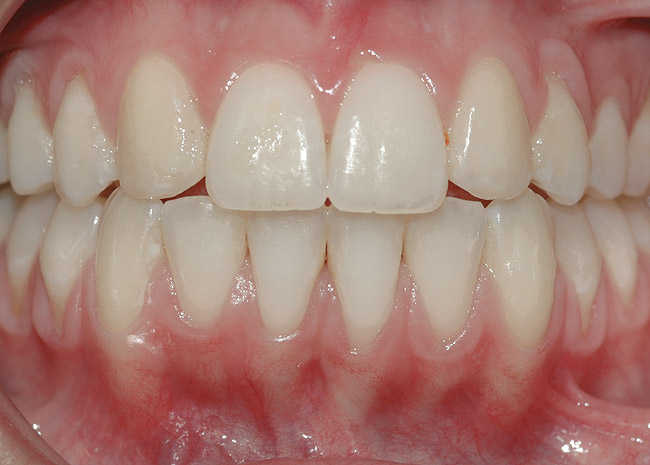

CASE 5 Fig 12. Post-orthodontic Miller Class I recession of lower left central incisor 9 months after completion of first orthodontic treatment.

Figure 12

Fig 13. Clinical view of same patient 2 years after orthodontic treatment only, showing almost complete spontaneous root coverage.

Figure 13

In Miller Class I recessions, orthodontic tooth movement alone may be sufficient. After correction of root position, spontaneous root coverage may occur, making surgical intervention superfluous (Figure 12 and Figure 13). However, if residual recession persists, the practitioner can choose either to follow up the case with SPT for 1 to 2 years, aiming for further spontaneous improvement, or proceed directly to surgical root coverage.